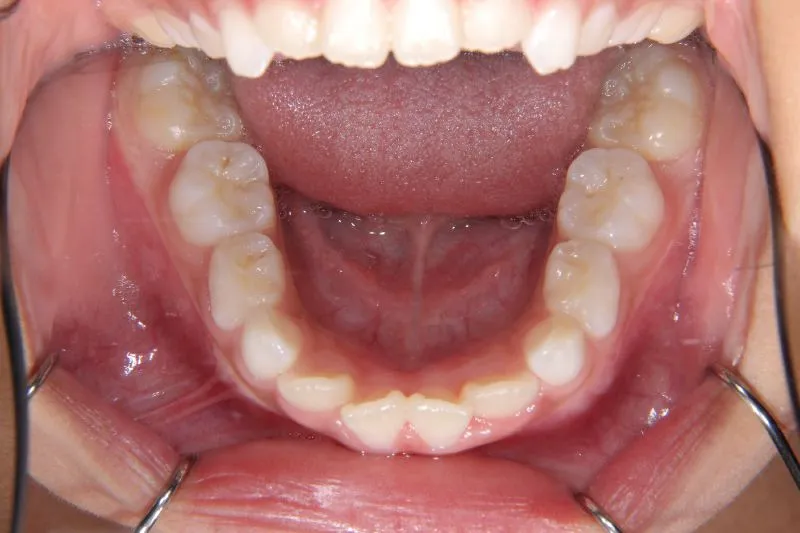

状態 前歯で噛めない(開咬/オープンバイト)

1.主訴 前歯がかみ合わない・出っ歯

2.診断名あるいは主な症状 開咬

4.治療に用いた主な装置 拡大床

前歯がかみ合っていません。

前歯は物を噛みちぎる(ハサミのような)役割をするのですが、歯と歯が離れていて本来の役割を果たしていません。